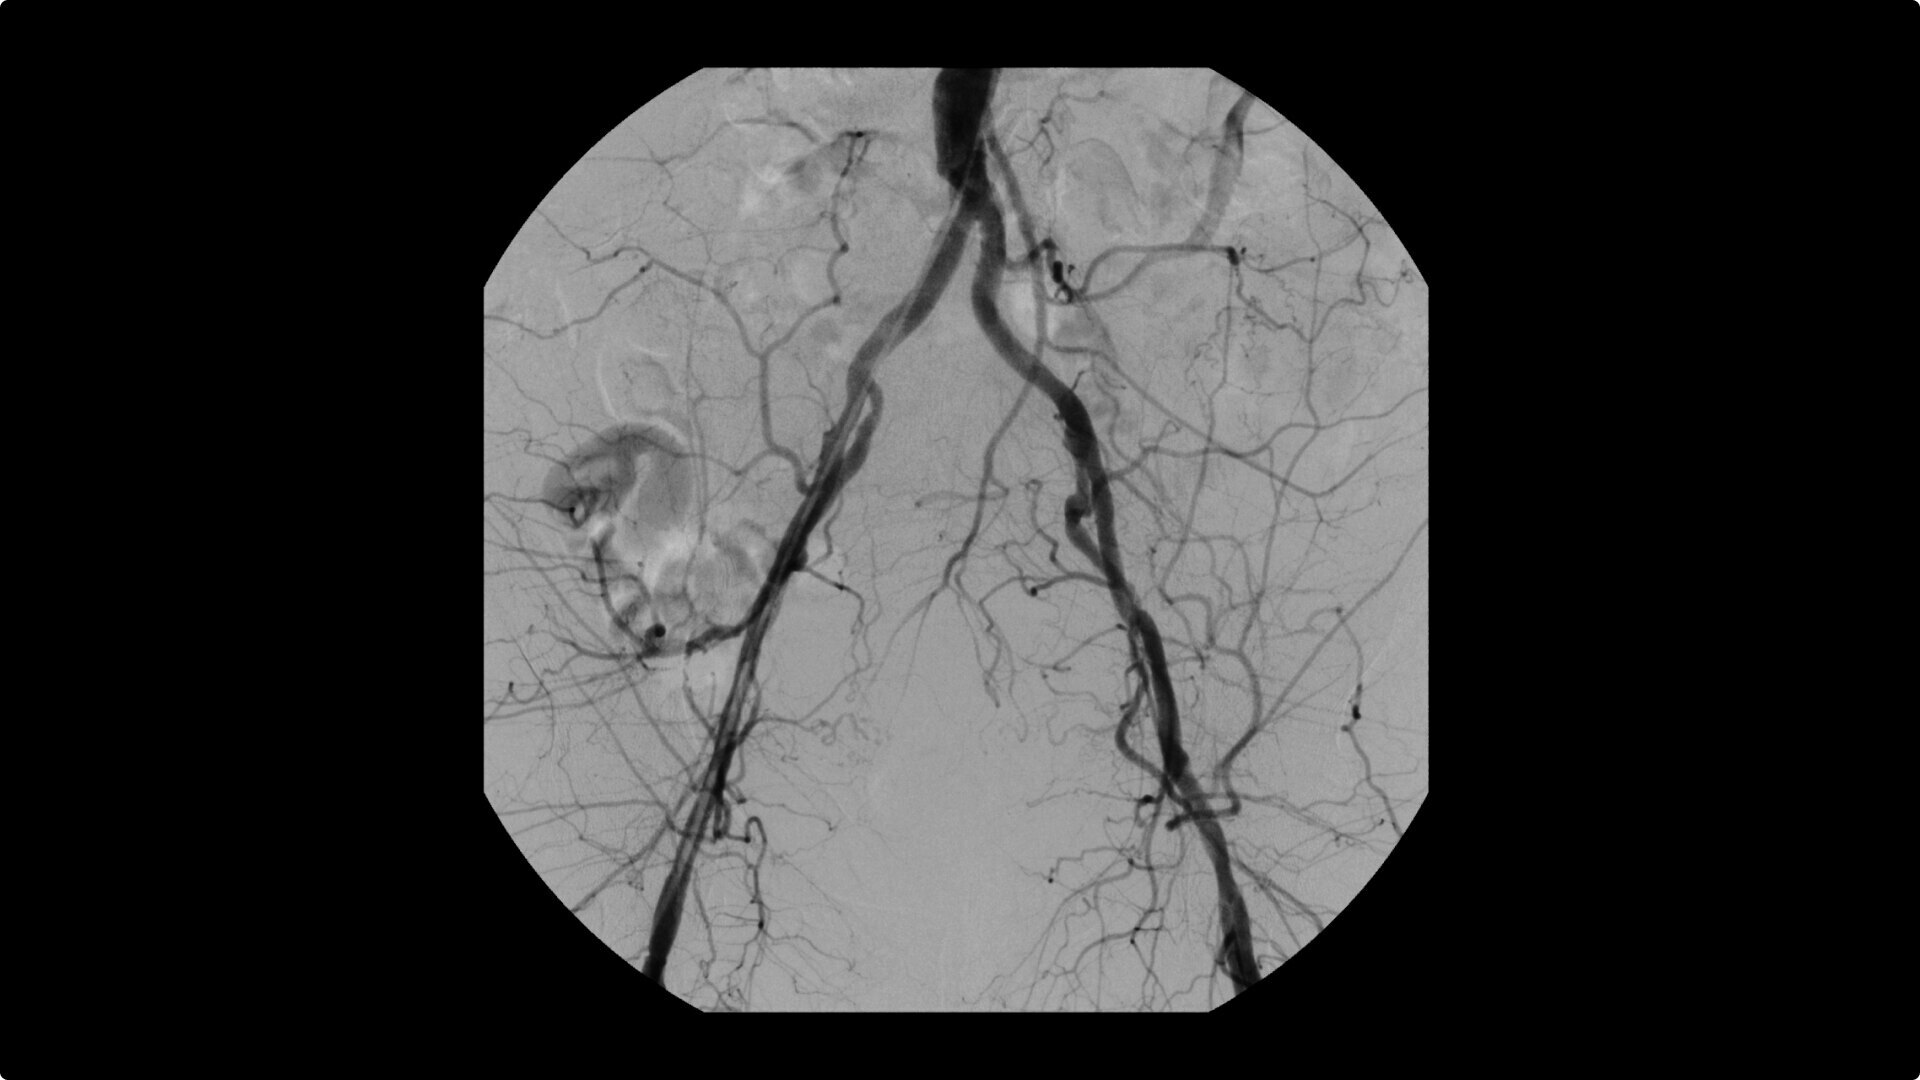

OEC C-arms are used by interventionalists and surgeons to obtain vascular imaging during peripheral to contrast run-off procedures. Superb resolution, even in the presence of motion, enables easy identification of anatomical landmarks and the extremity of the catheter, even as catheter tip moves.

Clearly see 0.014” guidewires in chest and abdomen region or 0.008” guidewires in peripheral vascular with the OEC Elite CFD with a flat detector, image processing advancements and 4K viewing display.

To see vessel stenosis or tips of guidewires, Live Zoom up to 4X during a fluoro or Cine without the additional dose of Mag modes or resulting X-ray tube heat buildup.

Conveniently plan procedures with comprehensive imaging tools to measure percent stenosis, distance, or angles, annotate and draw on images.